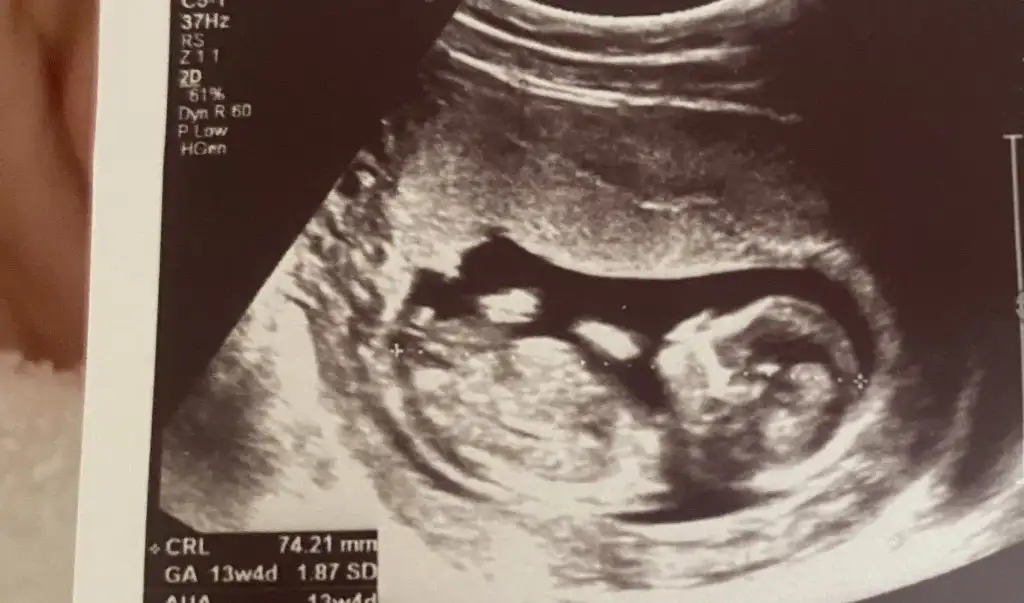

Ben snaki pipi gördüm gibi canımEki Görüntüle 3460091 Eki Görüntüle 3460092 Kızlar cinsiyet tahmini yapabilecek var mı 13 haftalığız

Bende öyle görüyorum sanki ama bilemedim.Doktor da bacak arasına bakmadı asistan bakmıştı doktor pozisyon erkeğe benziyor dediBen snaki pipi gördüm gibi canım